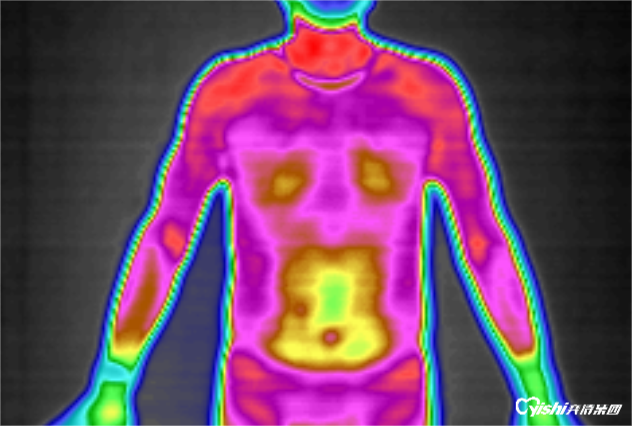

热成像扫描技术是近年来成功应用于临床的一项新的临床影像辅助诊断技术。医···

任何高于绝对零度-273.15℃的物体,由于原子和分子结构内部的无规则···

全维度热成像扫描系统(GTT)是新一代高精度多功能医用热成像扫描分析系···